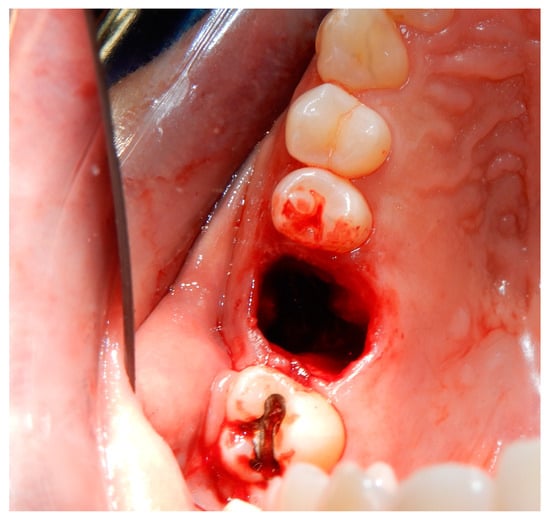

3.2. Case Report